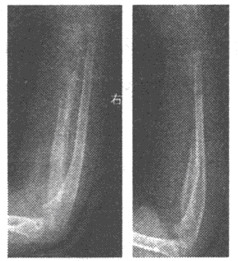

238、单项选择题

男,根据其正常膝关节影像图像,判断其最可能的年龄()

A.61岁左右

B.51岁左右

C.11岁左右

D.21岁左右

E.31岁左右